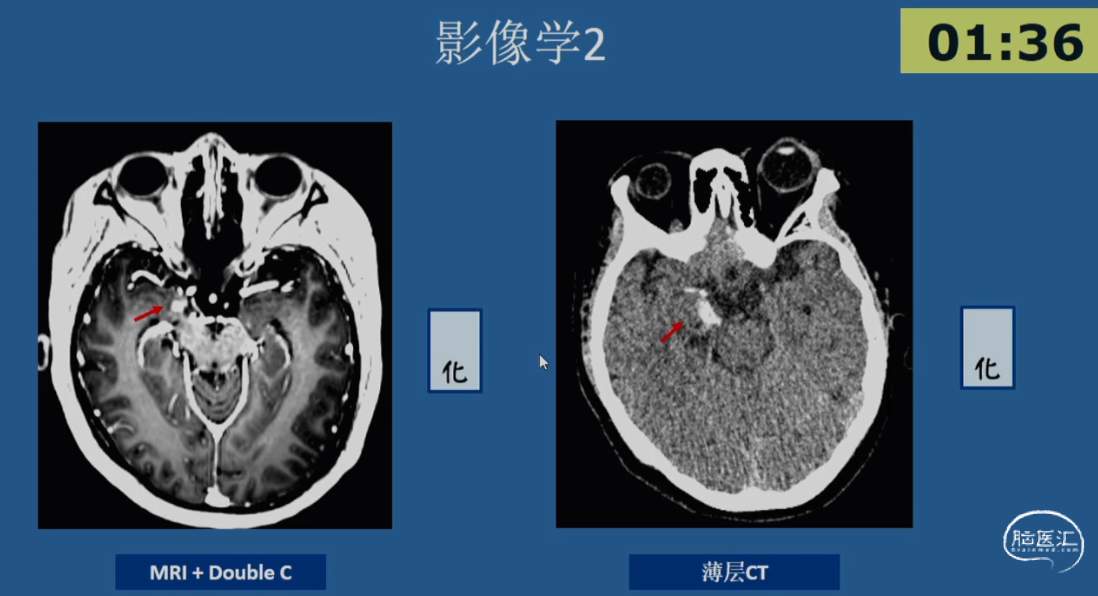

病例示例3 -简要病史

•患者,女性,20岁,右利手

•起病年龄:出生4月

•主要发作形式:伴有知觉受累的局灶性发作

-发作主要表现:发作前偶伴心悸、胸闷→后出现意识丧失伴眼神呆滞→数秒后出现身体向各方向不自主扭转,伴喉部发声(无四肢抽搐表现)→发作持续5-10min后意识恢复→发作后无头痛、头晕等不适

-【出生4月起】:初始发作频率1次/天,服用CBZ后发作可控;

-【12岁起】:发作频率再次↑为1次/天,加用药物后发作控制于5-10次/年;

-【19岁起】:多药联用控制不佳,发作频繁时可达3-4次/天,至少2-3次/月

•20岁时AEDs服用:CBZ 0.2g tid + LTG 100mg bid +CZP 0.5mg qn po

•既往史及家族史无殊,无热性惊厥史

•出生史:剖腹产,无早产、难产史,生长发育同同龄人;学历中专

•认知功能测评:MMSE 27分(延迟记忆-3),MoCA 27分(抽象-1,延迟回忆-2);WAIS-RC IQ 100分(语言IQ 92分;操作IQ 112分)

•情绪测评:HAMA 9分(轻度焦虑),HAMD 8分(轻度抑郁)

01.初步评估:

影像学表现:2018-03-05 MRI 常规MRI阴性

02.发作期评估

03.SEEG手术评估